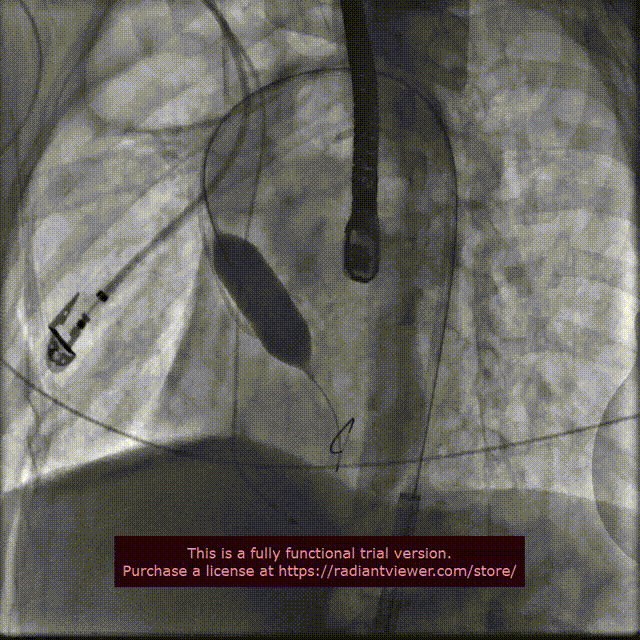

手术过程概览:

行主动脉根部造影后,直头导丝成功跨瓣,选择左冠切线位进行球囊预扩;TaurusElite AV23瓣膜送至主动脉弓,主动脉根部再次造影,并取零位释放位置。

球 囊 预 扩

瓣膜精准定位

在团队的密切合作下,瓣膜释放到工作位,行主动脉根部造影评估,明确定位良好,瓣膜缓慢释放,瓣架依次稳定脱钩,花冠完全展开。

释放到工作位

瓣膜缓慢释放,稳定脱钩

术中结合DSA、超声影像,多角度观察显示:瓣周漏及反流显著,遂决定球囊后扩,行18mm TaurusAtlas球囊进行后扩。

主动脉根部造影,瓣周漏显著

18mm球囊扩张,无冠窦形态欠佳

18mm TaurusAtlas球囊后扩张,超声显示瓣周漏及反流改善不明显,在瓣膜可能移位的风险下决定行20mm TaurusAtlas球囊后扩,结果效果理想,血流动力学显著改善。

20mm球囊扩张

主动脉根部造影,血流动力学稳定,微量反流